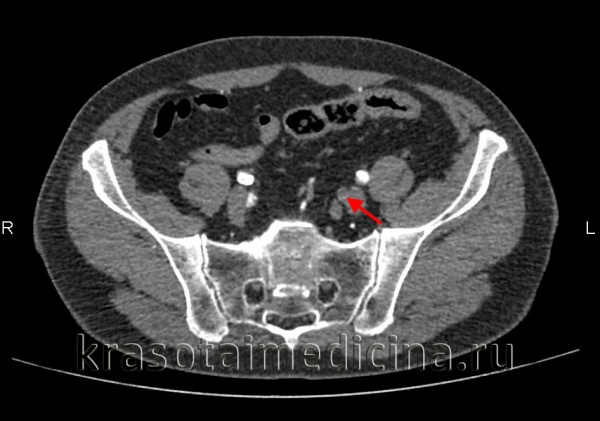

КТ-ангиография брюшной аорты и ее ветвей. Полная окклюзия просвета левой внутренней подвздошной артерии